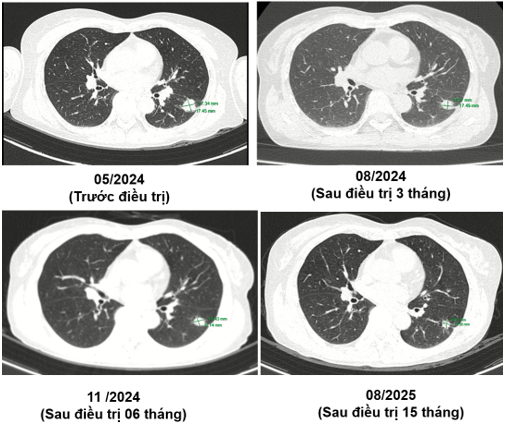

CT ngực (05/2024):

Hình 2: Hình ảnh tốt đặc ở phân thùy S6 phổi trái, đường kính 17 mm, bờ tua gai. Không thấy hạch trung thất to.

Hình 3: Các nốt đặc rải rác phổi trái, bờ đều, đường kính ~ 5mm - theo dõi tổn thương thứ phát.

Ct ngực sau điều trị:

Theo dõi định kỳ bằng lâm sàng, chụp CT ngực và MRI sọ não sau 3 tháng, 6 tháng và 15 tháng cho thấy:

- Tổn thương phổi và não giảm kích thước rõ rệt.

- Không xuất hiện tổn thương di căn mới.